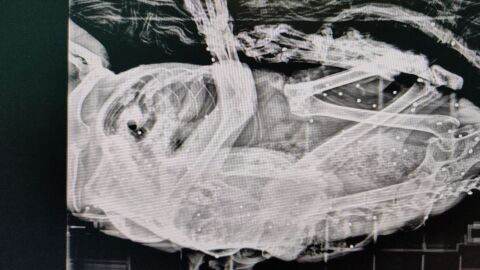

La asociación Gatucos Torrelavega ha atendido recientemente a un gato procedente de una colonia felina de Posadillo (Polanco) que albergaba más de 50 perdigones en su cuerpo. Se trata de Van Gogh, un animal que había sido intervenido quirúrgicamente por un carcinoma en la oreja y se encontraba recuperándose en el refugio cuando comenzó a mostrar cojera persistente. Tras su traslado al veterinario y la realización de pruebas radiológicas, se detectaron los perdigones en su interior.